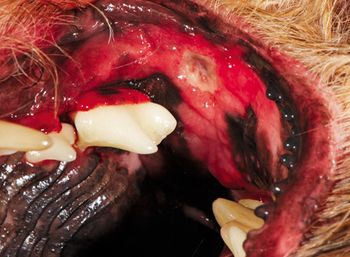

This veterinary dental condition, also called kissing lesions, can be extremely painful in affected pets and requires immediate and dedicated care.